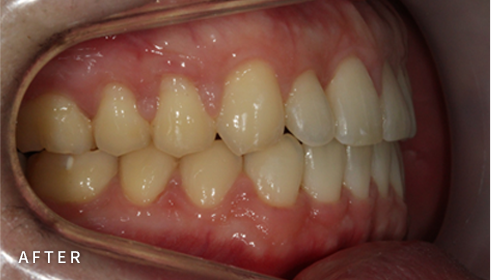

설측교정은 치아 안쪽(설측면)에 초소형 장치로 보이지 않게

아름다운 미소를 만드는 고난이도 프리미엄 교정 치료입니다.

난이도가 높은 만큼 풍부한 진료 경험이 중요합니다.

강남에서 다년간 설측교정에 특화된 경험을 바탕으로,

3D 디지털 기술을 활용한 맞춤 설계, IDBS방식을 통한

정밀하고 불편감 없는 치료를 제공합니다.